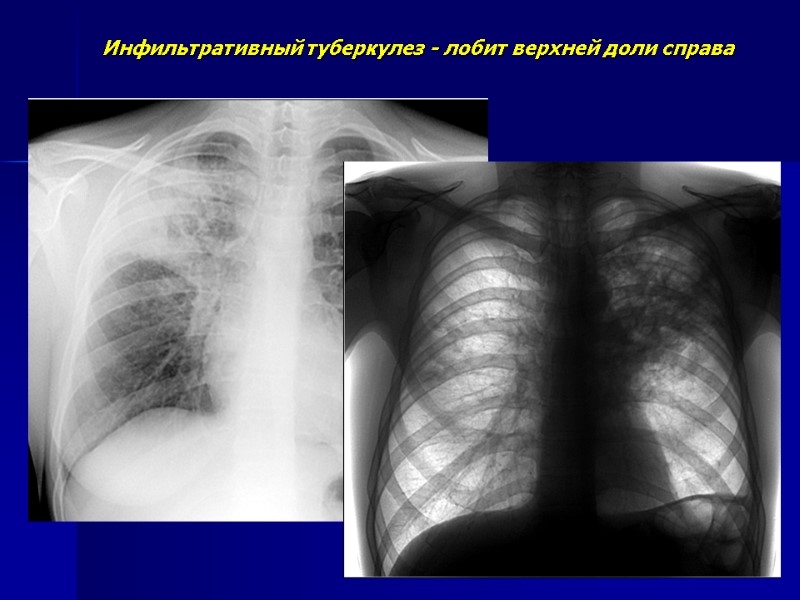

Инфильтративный туберкулез - лобит верхней доли справа